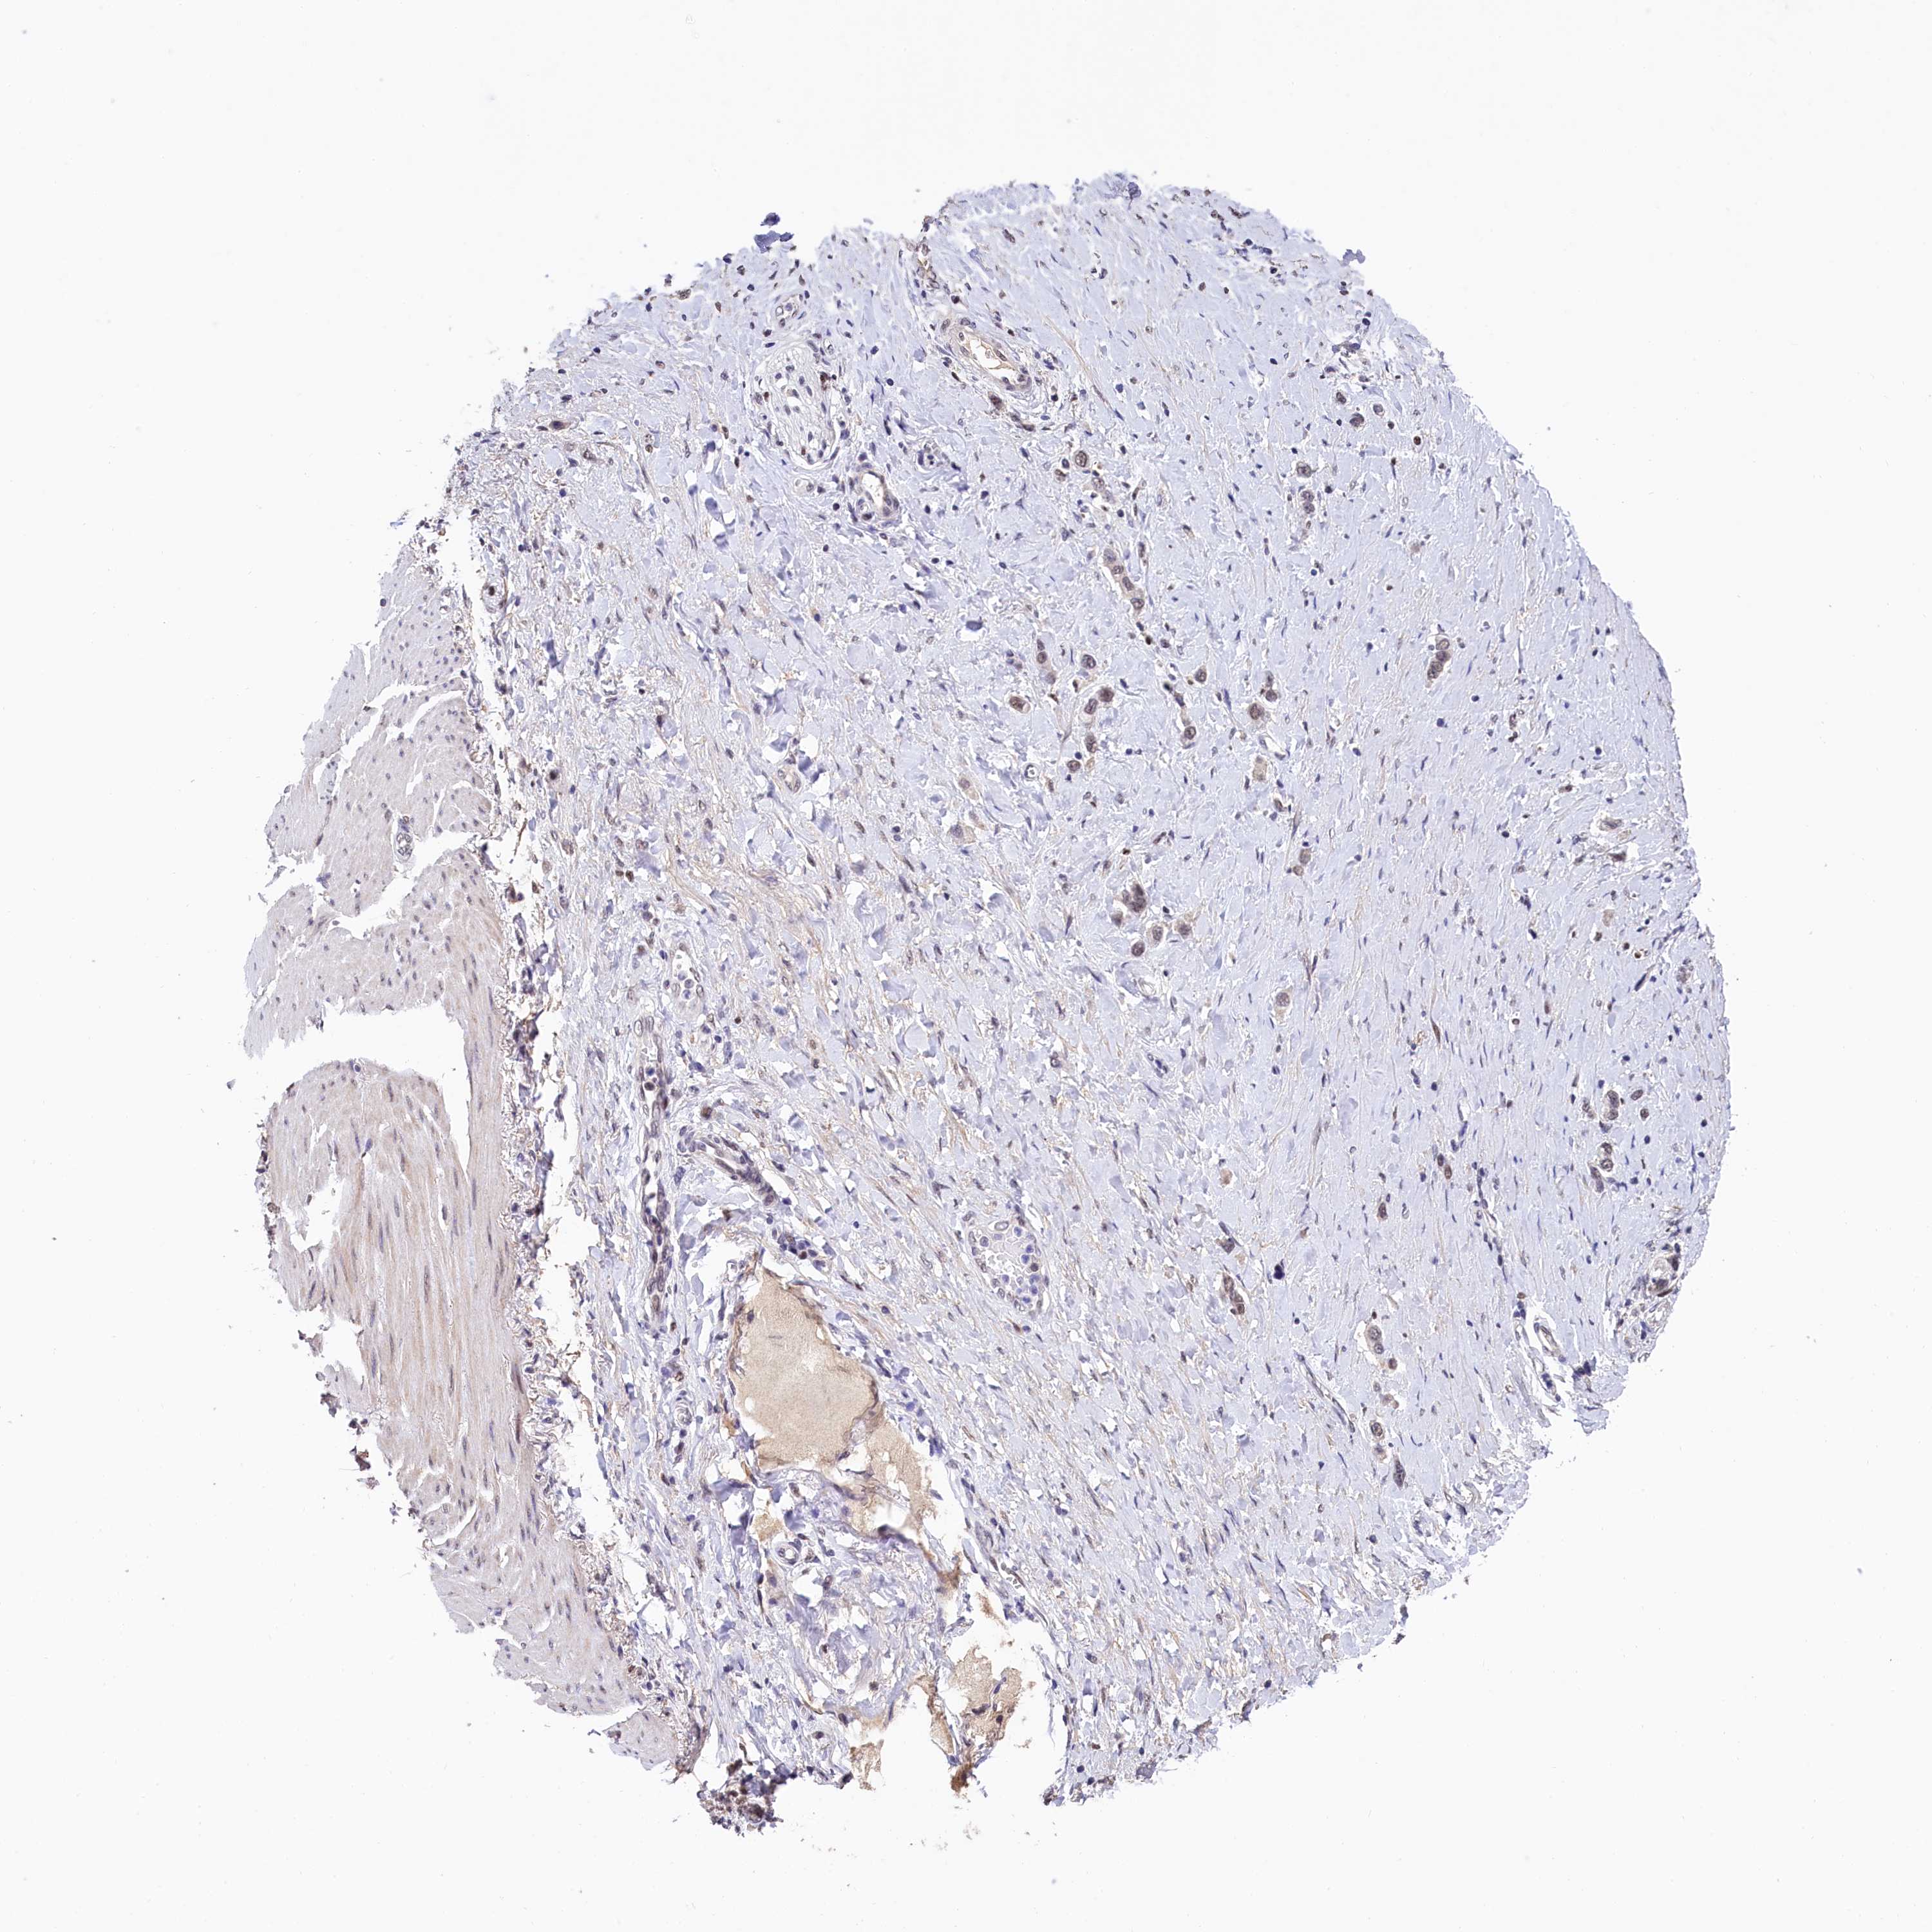

STOMACH CANCER - Protein expressioni

A mouse-over function shows sample information and annotation data. Click on an image to view it in a full screen mode. Samples can be filtered based on level of antibody staining by selecting one or several of the following categories: high, medium, low and not detected. The assay and annotation is described here.

Note that samples used for immunohistochemistry by the Human Protein Atlas do not correspond to samples in the TCGA dataset.

Antibody stainingi

Antibody staining in the annotated cell types in the current human tissue is reported as not detected, low, medium, or high, based on conventional immunohistochemistry profiling in selected tissues. This score is based on the combination of the staining intensity and fraction of stained cells.

Each image is clickable and will lead to virtual microscopy that enables deeper exploration of all samples and also displays staining intensity scores, fraction scores and subcellular localization as well as patient and tissue information for each sample.

Antibody HPA041062

Antibody HPA045473

Staining

High

Medium

Low

Not detected

Intensity

Strong

Moderate

Weak

Negative

Quantity

>75%

75%-25%

<25%

None

Location

Nuclear

Cytoplasmic/membranous

Cytoplasmic/membranous,nuclear

Adenocarcinoma, NOS